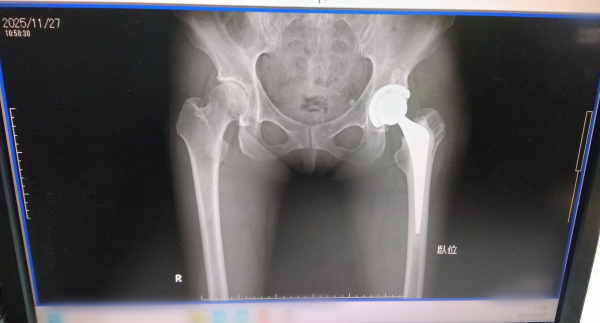

手術で大腿骨頭をカットするのですが

手術前に、骨を寄付してくださいと、

同意書を書きました

先生に股関節の後でいいのですか、腰痛も見てほしいです

腰スベリ症と言われ

腰骨から、足首までのしびれが酷くて